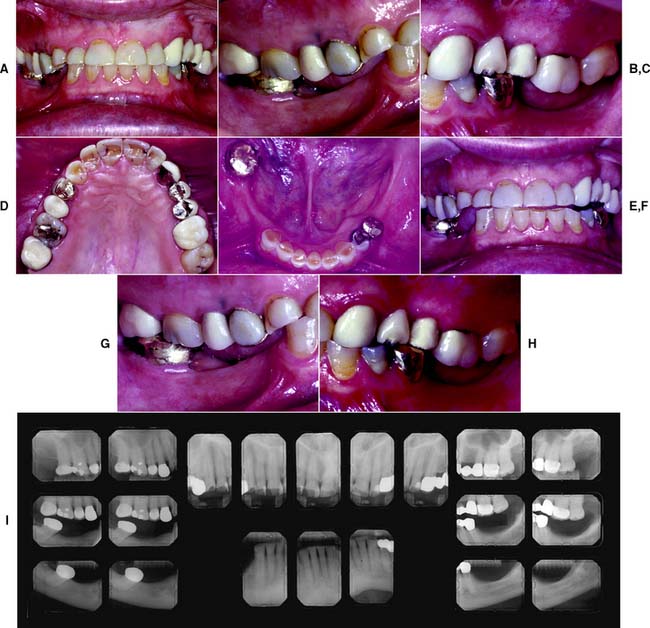

This class (Figs. 1-31 and 1-32) is characterized by substantially compromised location and extent of edentulous areas in both arches, abutment condition necessitating substantial localized adjunctive therapy, occlusal characteristics necessitating reestablishment of the entire occlusion without a change in the occlusal vertical dimension, and residual ridge conditions.

Fig. 1-31 Class III patient. This patient is categorized as Class III because the edentulous areas are located in both arches and there are multiple such locations within each arch. The abutment condition is substantially compromised as a result of the need for extracoronal restorations. There are teeth that are extruded and malpositioned. The occlusion is substantially compromised because reestablishment of the occlusal scheme is required without a change in the occlusal vertical dimension. A, Frontal view, maximum intercuspation. B, Right lateral view, maximum intercuspation. C, Left lateral view, maximum intercuspation. D, Occlusal view, maxillary arch. E, Occlusal view, mandibular arch. F, Frontal view, protrusive relationship. G, Right lateral view, right working movement. H, Left lateral view, left working movement. I, Full-mouth radiographic series.

(From McGarry TJ, et al: Classification system for partial edentulism. J Prosthodont 11:181, 2002.)